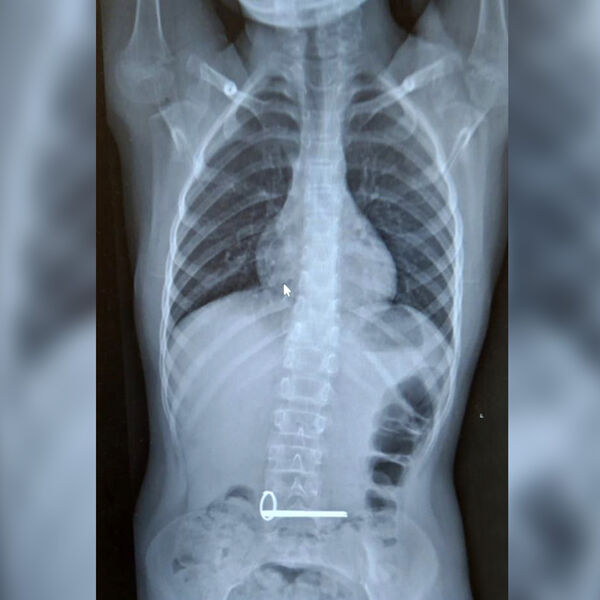

Школьник поступил в отделение экстренной помощи с подозрением на инородное тело в желудке. В ходе обследования было установлено, что мальчик проглотил два металлических ключа.

Эндоскописты извлекли ключи без каких-либо осложнений для ребенка, манипуляцию провели под наркозом. Жизни и здоровью несовершеннолетнего ничто не угрожает.